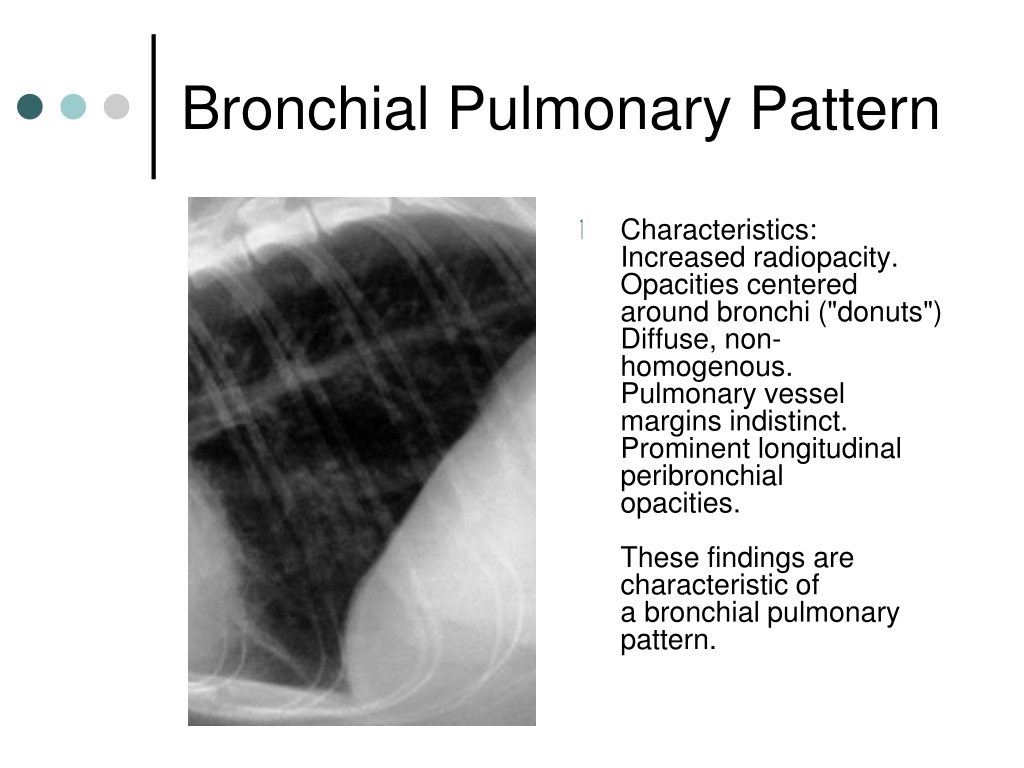

Bronchial Pattern In Dogs - Bronchial pattern is caused by thickening and increased prominence of the bronchial walls, usually secondary to chronic inflammation. Web bronchial lung pattern the bronchial pattern is obtained when the bronchial wall is infiltrated by cells or fluid or when the peribronchial space is replaced by cells or fluid. White lines indicate areas where a pleural fissure line would occur when an effusion is present. A bronchial pattern is an abnormal lung opacity caused by peribronchial cellular, fluid and fibrotic infiltration, or bronchial mucosal and submucosal. Web tracheobronchitis is a sudden or longterm inflammation of the trachea and bronchial airways; The incidence in dogs is twice that in cats;. If the cough lasts more than two months, it's generally referred to as chronic bronchitis. Kalin spasov1, michaela kunovska2, dimo dimov3. Impingement on the main stem bronchi by severe left heart enlargement; Web a bronchial pattern is diffuse thickening of the airway walls giving the appearance of thick lines and rings throughout the lungs.

It may also extend into the lungs. Web bronchial lung pattern the bronchial pattern is obtained when the bronchial wall is infiltrated by cells or.

A bronchial pattern is an abnormal lung opacity caused by peribronchial cellular, fluid and fibrotic infiltration, or bronchial mucosal and submucosal. White lines indicate areas where a pleural fissure line would occur when an effusion is present. Kalin spasov1, michaela kunovska2, dimo dimov3. Web bronchial lung pattern the bronchial pattern is obtained when the bronchial wall is infiltrated by cells or fluid or when the peribronchial space is replaced by cells or fluid.

Web A Bronchial Pattern Is Diffuse Thickening Of The Airway Walls Giving The Appearance Of Thick Lines And Rings Throughout The Lungs.